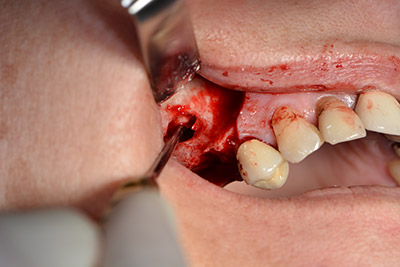

The classic incision (crestal, buccal relief) and the preparation of the mucoperiosteal flap enabled a good overview.

Sky implants (bredent) were used this case. The surgical protocol of these, specify pilot drilling at about 1200 rpm (Fig. 9).

The fenestration was prepared at 35,000 rpm and then the nasal mucosa were prepared in the cranial direction (Fig. 13 to 14).